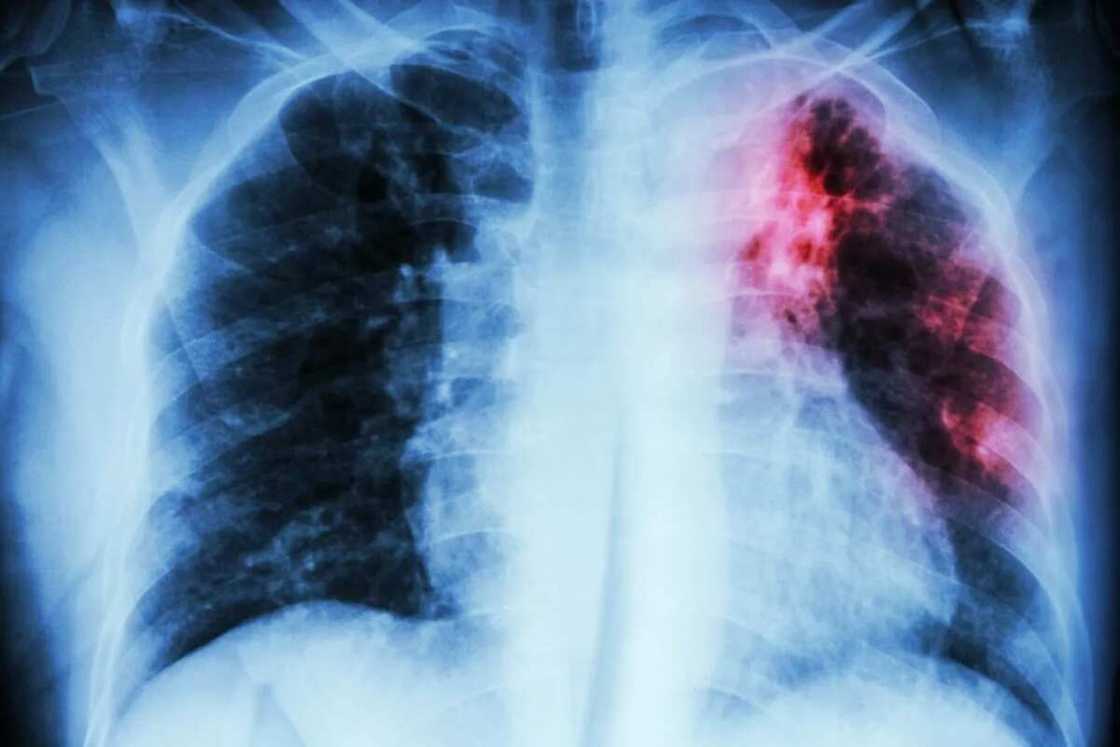

Source: Depositphotos